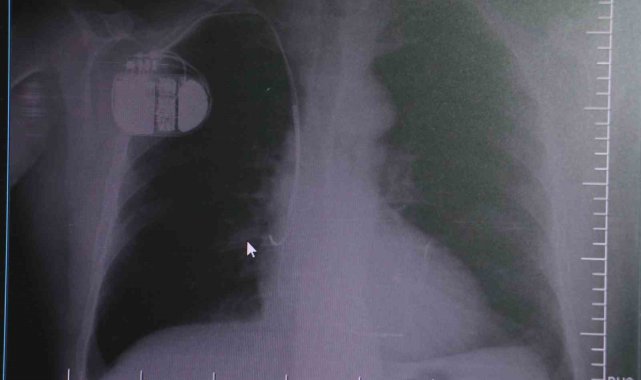

Sivas Medicana Hastanesi Kardiyoloji Uzmanı Dr. İsmail Erdoğu, özellikle kalp pili tedavisinin ani ölümleri önlemede büyük rol oynadığını belirterek, soğuk havalarda kalp pili kullanan hastaların dikkatli olması gerektiği konusunda uyarılarda bulundu.Dünya genelinde kalp hastalıkları, ölüm nedenleri arasında ilk sıralarda yer alıyor. Kalp rahatsızlıkları yalnızca damar tıkanıklığı yaşayan hastalarla sınırlı olmamakla birlikte tansiyon ve şeker hastaları da kalp hastalıkları açısından yüksek risk grubunda bulunuyor. Geçmişte kalp krizi sonrası hastaların yaşam şansı oldukça düşükken, günümüzde erken müdahale ile hayatta kalma oranı büyük ölçüde arttı. Ancak kalp krizinden kurtulan hastalarda zamanla kalp dokularında hasar oluşabiliyor ve bu durum kalp yetersizliği ile ritim bozukluklarına yol açabiliyor.Konuya ilişkin açıklamalarda bulunan Sivas Medicana Hastanesi Kardiyoloji Bölümü Uzmanı Dr. İsmail Erdoğu, kalp pilinin önemine vurgu yaptı. Erdoğu, Yeni nesil kalp pillerinin MR cihazlarına girmeye imkan sağladığı, ancak tarama cihazlarından geçmenin önerilmediğini ifade ederek, "Soğuk hava nedeniyle oluşan titremeler, kalp pilinin kalbin durduğunu sanmasına ve yanlış şoklamaya yol açabilir. Bu nedenle hastalarımızın bu dönemlerde daha dikkatli olmalarını öneriyoruz" dedi."Kalp piline ihtiyaç duyuluyor"Kalp krizleri sonrası kalp dokusunun zarar gördüğünü söyleyen İsmail Erdoğu, "Dünyada artık kalp hastalıkları en sık ölüm sebeplerinden biri. Kalp hastalıklarında çok fazla grup var. Biz kalp hastalıkları deyince sadece kalbinde stent olan ve damarlarında sorun bulunan insanlardan bahsetmiyoruz. Aynı zamanda tansiyon ve şeker hastaları da kalp hastalıklarına aday. Toplumun yaklaşık yüzde 30-35'lik bir kısmını kapsıyoruz. Çok yaygın bir hastalık ve bu hastalıkta teknolojik kapsamda, ilaç konusunda son 30 yılda çok ciddi gelişmeler oldu. Geçmişte insanları hastanelerde kalp krizinden dolayı kaybederken şimdi hastaneye başvurular sonrasında yaşama tutunmak büyük oranda mümkün. Yaşanan ölümler ise genellikle hastaneye gelmeden önce gerçekleşmekte. Kalp krizinden kurtulmanın hastalarda belli bir bedeli oluyor. Kalp krizi sonrası kalpteki dokular zarar görüyor ve kalp yetersizliği oluşuyor. Bu kalp yetersizliği olan kalplerde ritim bozuklukları ve ani ölümler gibi sorunlar gündeme gelebiliyor. Bunlardan uzun vadede korunmak için hastalarda mutlaka bir kalp piline ihtiyaç duyuluyor" dedi."Soğuk havalarda temkinli olunması gerekiyor"Kalp pilleri ile MR cihazına girilebileceğini belirten Erdoğu, "Çok büyük bir ameliyat değil ama yine de ciddi bir cerrahi işlem. Kalp pili, tıpta son 30 yılda yaşanan gelişmelerden en büyüğü. Bir bilgisayarın küçültülüp insan vücuduna konulmuş hali aslında. İnsan ömrünü ciddi oranda uzatan bir tedavi. İnsanlar bir şokla hayata tutunurken, pil olmasaydı öleceğini düşündüğümüz birçok hastamız var. Kalp pilinin bu özelliği, uygun hastalarda ciddi oranda ani ölümü engelliyor. Hastanın başına gelecek bir kalp durması durumunda yanında bir sağlıkçı yoksa, onun ritmini düzeltecek defibrilatör cihazı yoksa hastayı hayatta tutmak mümkün değil. Uygun endikasyonlarda kalp pili olduğu zaman, pil hastaların ritmini algılıyor ve acilde yapılan şoklamayı yaparak hastayı hayata döndürüyor. Kalp pillerinde yeni teknolojilerle MR'a girmek mümkün, tomografiye zaten girebiliyorlar. Tarama cihazlarından geçmelerini uygun görmüyoruz. Bu tarz durumlarda hastalarımız 'kalp pilim var' dediğinde muaf tutuluyorlar. Kalp pilleri ciddi teknolojik cihazlardır. Vücudun içindeki titreşimi, örneğin mikser kullanmak, kolunu sallayacak herhangi bir eylem kalp pilinde olumsuz etki oluşturabilir. Soğuk havalarda vücutta oluşan ciddi titremeler kalp pilinin hafızasını karıştırıp kalbin durduğunu düşündürebilir ve gereksiz şoklama yapabilir. Bu tarz kişilerin soğuk havalarda daha temkinli olması gerekir" diye konuştu.